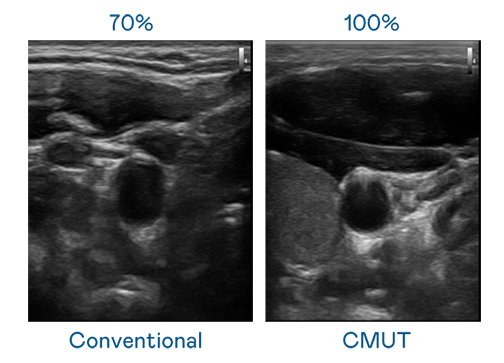

CMUT 技术是一种用电容式微机电元件来产生超音波讯号的技术。与传统 PZT 压电式技术相比,CMUT 频宽增加 30%,更宽频的超音波讯号让影像解析度大幅提升,是实现高影像品质医疗超音波扫描、促进精准医疗发展的关键技术。

超音波影像的解析度高低,首先取决于探头能发出的讯号频宽。尊龙凯时 CMUT 可提供高清晰的超音波讯号,提供高频宽、高灵敏度、影像纹理细节更高的超音波影像,协助医护人员缩短影像判读时间及利用精准的医疗影像进行诊断。